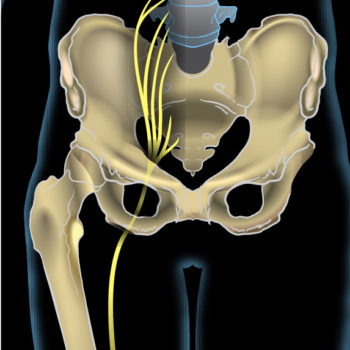

What is it? Sciatica is the name given to any irritation or compression to the sciatic nerve. The sciatic nerve is the longest nerve in your body. It runs from the back of the pelvis and all the way down both legs, finishing at your feet. It can cause pain, numbness and a tingling sensation […]